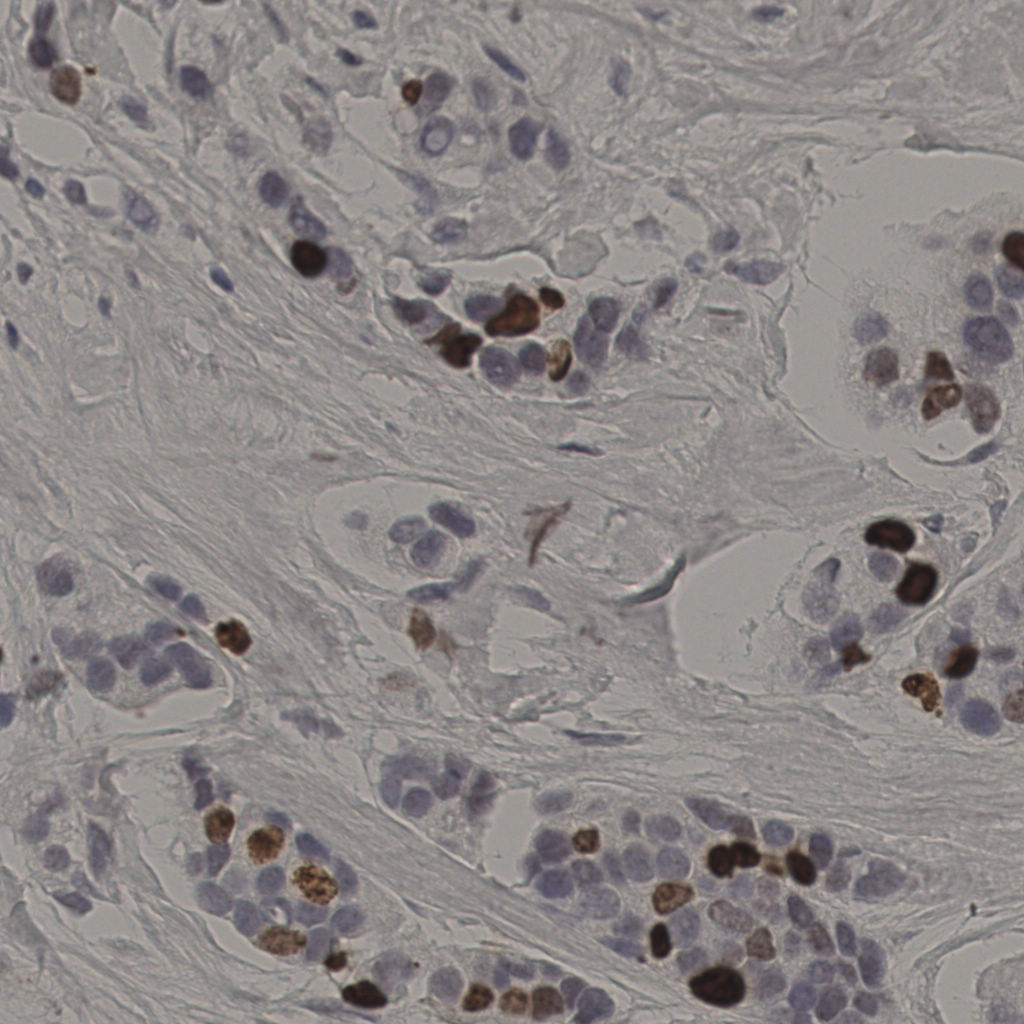

17.75%

Ki67 指数

阴 7986

阳 1723

切片统计

总切片

2640

有效

412

已标记

412

有效率

16%